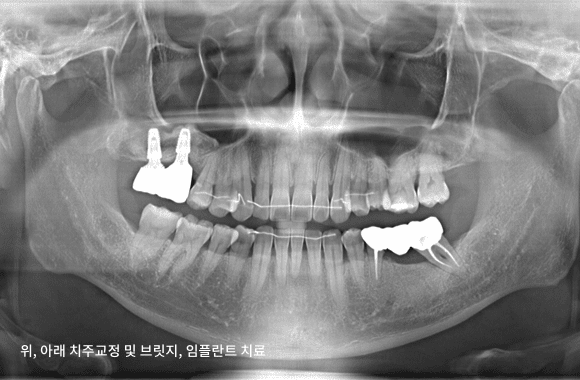

시니어 교정+임플란트